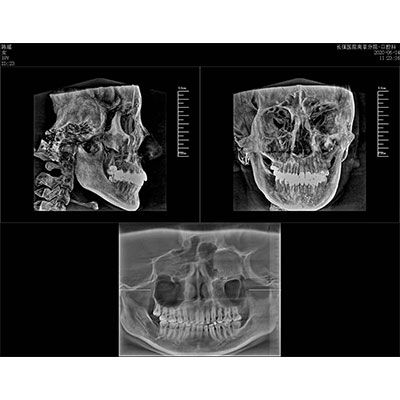

該款牙科CBCT產(chǎn)品采用動態(tài)平板探測器,獲得三維圖像的同時還具有數(shù)字化全景功能,廣泛應(yīng)用于口腔頜面外科、正畸科、正頜外科、種植科、牙體科、顳下頜關(guān)節(jié)科等術(shù)前術(shù)后。

專有三維重建算法,可提供任意位置高清斷層影像。

可同時觀察軸向面、冠狀面和矢狀面圖像,方便臨床診斷。